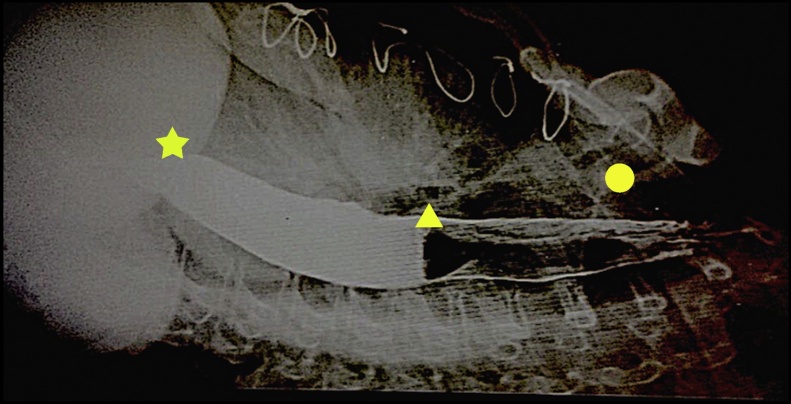

Barium oesophagram (Fig. 3) showed tapering at the gastro-oesophageal junction, a mildly dilated, aperistaltic oesophagus, and delayed passage of contrast into the stomach.

Fig. 3.

The star shows the birds head and neck which is where the distal oesophagus tappers off. The triangle is in the area of the body and tail of the bird which is representative of the dilated portion of the oesophagus with food debris. The circle shows one rib of the thoracic cage encircling the bird.